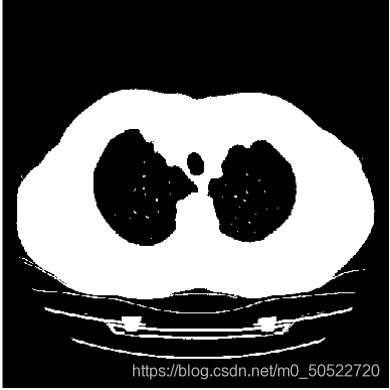

(3)迭代分割

迭代分割是逼近思想,将通过程序不断迭代出所需要的阈值,再对图像二值化处理。将背景与人体进行分离,背景的灰度值赋值为0,人体的灰度值赋值为255。即可得到二值图。

(4)二值图像连通区域标记(人景分割)和图像孔洞填充

使用图像孔洞填充消除肺质中的孔洞。连通分量标记(或者称连通分量分析,连通区域标记)是图论应用中的一种算法,给二值图像中的每个连通区域标上一个特定的标号。该算法可用来对图像的目标进行定位和计数。已知每个孔洞的一个点后,我们的目的就是用前景像素填充所有孔洞。